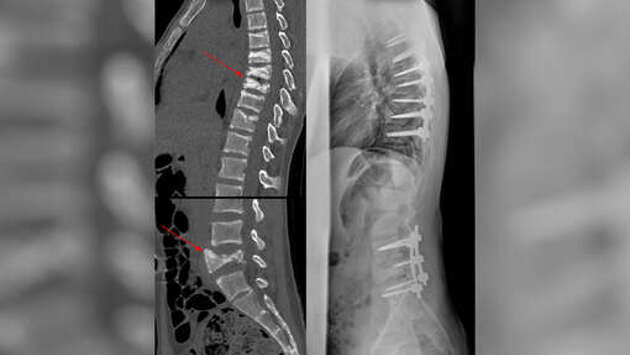

Медики из Китая и Европы обнаружили, что заживление поврежденных межпозвоночных дисков у пациентов с грыжей можно значительно ускорить с помощью инъекций синтетических аналогов белка муцина. Эти инъекции защищают диски от атак иммунных клеток, пишет ТАСС со ссылкой на пресс-службу шведского Университета Уппсалы. "Созданный нами подход дает новую надежду для пациентов, страдающих от болей в спине в результате развития межпозвоночной грыжи", - отметил научный сотрудник университета Янь Хунцзи. Он добавил, что это может предотвратить дальнейшие повреждения после удаления пораженных участков дисков, что существенно улучшит качество жизни таких пациентов. Ученые сделали этот вывод, протестировав свою терапию, которая подавляет патологические иммунные реакции после удаления поврежденных дисков. Эти нарушения в работе иммунной системы могут возникать, когда иммунные клетки начинают воспринимать студенистое ядро диска как чуждое вещество. Исследователи предположили, что проблему можно решить, если покрыть поврежденные участки диска гелеобразным материалом на основе синтетических аналогов белка муцина. Это вещество часто используется опухолевыми клетками и патогенами как барьер от иммунной системы, что навело медиков на мысль о его применении для защиты поврежденной части позвоночника.